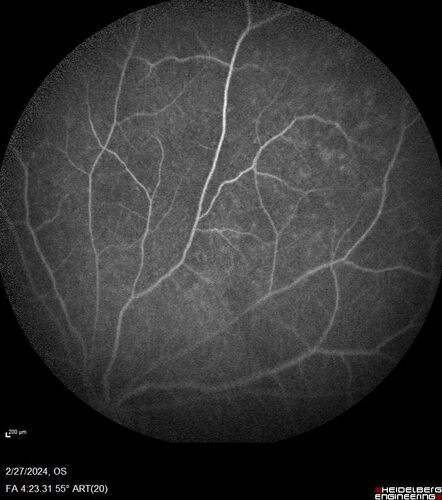

Syphilitic Chorioretinitis

41 year old man with vision loss for five days left eye. VA 20/32, 20/200

Syphilitic Chorioretinitis Both Eyes